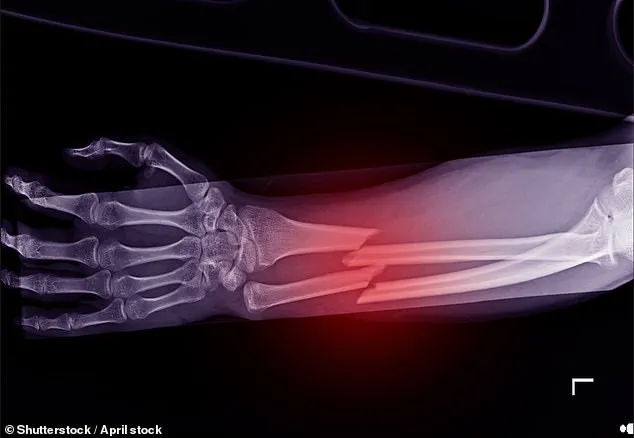

These services are critical for identifying the disease before it leads to life-threatening fractures, particularly in post-menopausal women, who are disproportionately affected.

The disease affects 3.5 million people in the UK, with one in two women over the age of 50 expected to break a bone due to osteoporosis.

These treatments can significantly reduce the risk of life-threatening hip fractures, a common and often fatal complication of the disease.

The National Institute for Health and Clinical Excellence (NICE) reports that more than a quarter of hip fracture patients die within a year, with one in ten dying within a month.